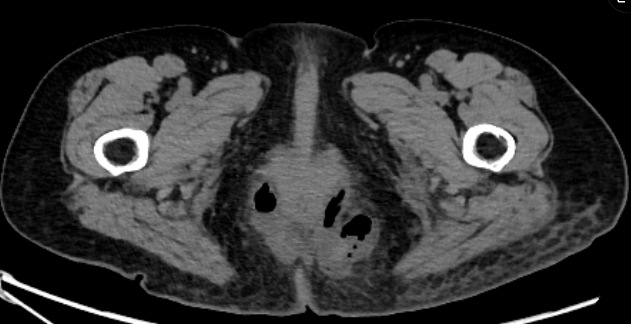

患者因肛周剧烈疼痛伴高热来院就诊,普外科医师孟光冉接诊后,迅速为其完善相关检查。经诊断,患者为“高位复杂性肛周脓肿(马蹄形)”。此类脓肿位置深、范围广,呈马蹄形环绕肛管,感染严重,已形成复杂脓腔与瘘管,治疗难度极大。加之患者年届78岁,身体机能下降,合并症风险较高,对麻醉与手术的耐受能力构成严峻考验。

面对这一棘手情况,医院迅速组织多学科会诊,为患者制定了精细化、个体化的改良Hanley手术方案。该术式是治疗复杂性肛周脓肿及肛瘘的经典方法之一,普外科团队在传统基础上进行了关键步骤的优化与改良:一是精准清创。术中精细探查,彻底清除坏死组织与感染病灶,从源头控制病情;二是引流通畅。通过改良切口设计,确保术后深部脓腔低位、充分引流,避免感染残留;三是功能保护。手术全程注重保护肛门括约肌功能,最大程度预防术后肛门失禁等并发症。